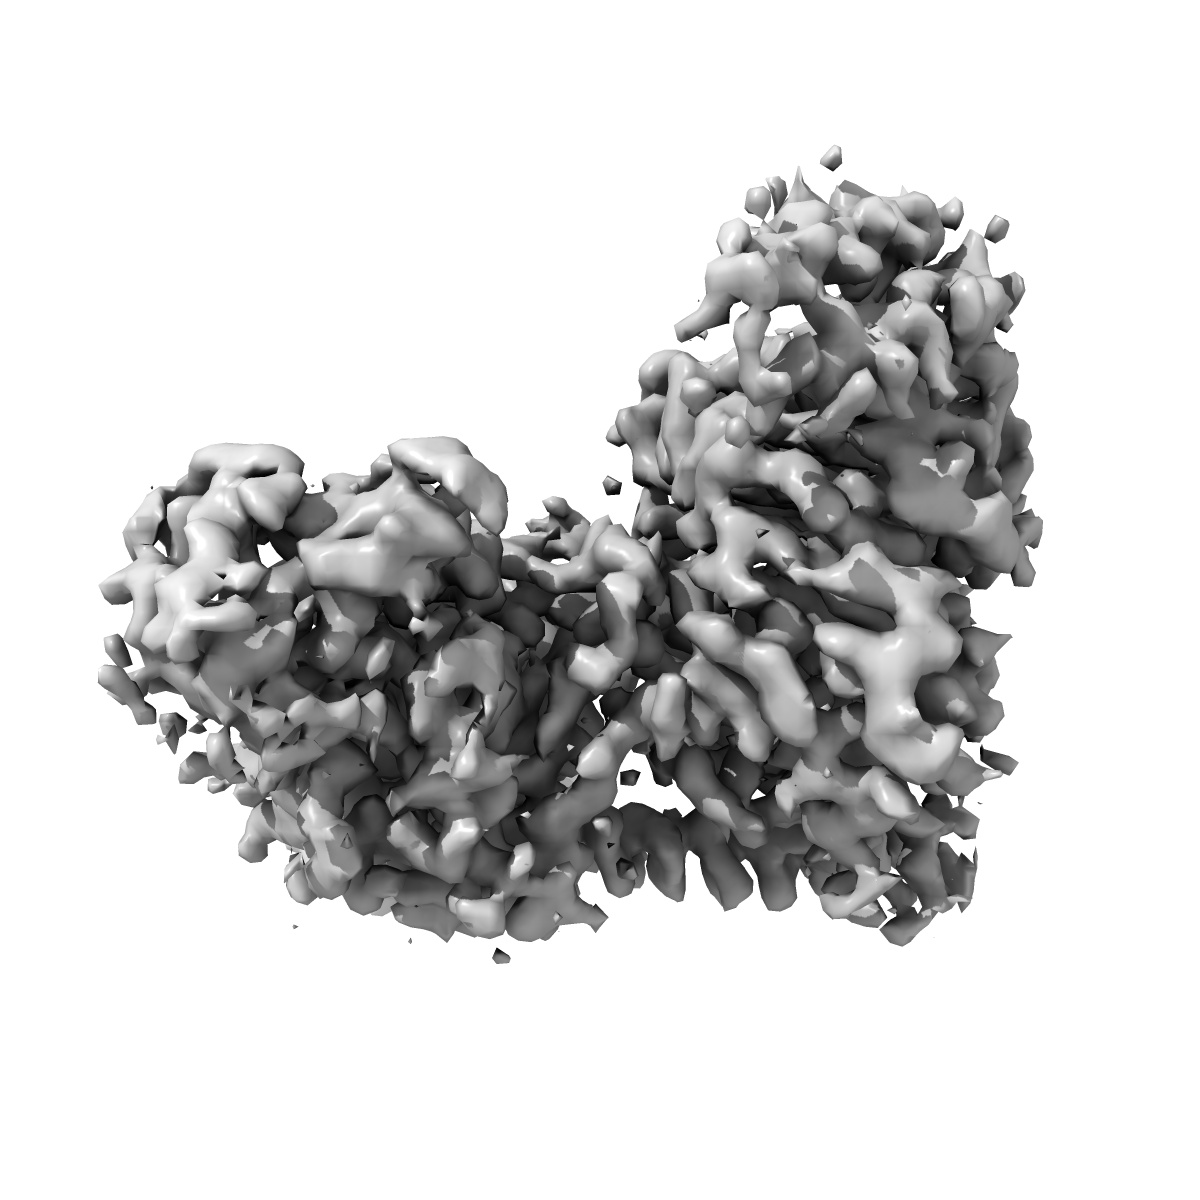

EMD-23281

Cryo-EM structure of the human adenosine A1 receptor-Gi2-protein complex bound to its endogenous agonist

Single-particle3.3 Å

Sample: Human adenosine A1 receptor-Gi2-protein complex bound to its endogenous agonist adenosine